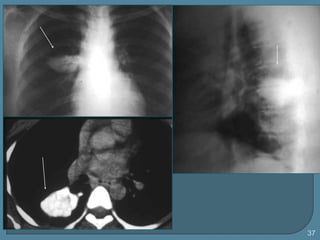

 Radiografía:

opacidad de 1-20 cm de D o

calcificaciones

 TC densidad de tejido graso

37